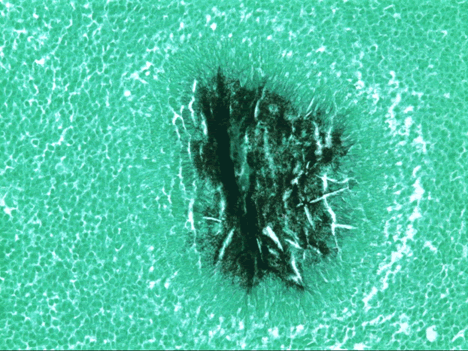

| Figure 1: PA chest film reveals a left pleural-based mass with pleural thickening and upper lobe scarring. |

PA and lateral chest film revealed patchy consolidation of the left lung with a large pleural-based mass, left apical pleural thickening, and right upper lobe scarring (Figure 1). Helical CT scan of the chest, abdomen, and pelvis with contrast demonstrates a large, 10.8 x 4.1 cm left pleural-based mass extending into the chest wall and left breast (Figure 2). There was periosteal thickening and irregularity of adjacent ribs. Multiple enlarged mediastinal, left hilar, and supraclavicular nodes were noted, the largest 1.5 x 2.6 cm in the AP window or station five region. There was patchy consolidation of the left and right upper lobes. An MRI of the thorax with contrast was obtained and confirmed the presence of left supraclavicular adenopathy and an enhancing mass with extension into the chest wall involving the ribs, infiltration of the pectoralis muscle, and extension into the left lung parenchyma. The main differential diagnoses at this time were neoplasm (sarcoma, advanced lung cancer, mesothelioma, lymphoma, osteosarcoma).